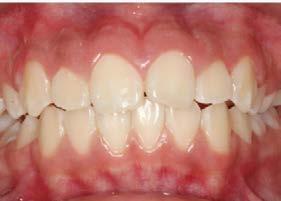

Objetivos: Conseguir clase I canina, controlar el crecimiento vertical, disminuir la convexidad esqueletal, reducir la sobremordida horizontal y mejorar el perfil facial. Caso clínico: Paciente femenina de 9 años, clase II esqueletal, biotipo dolicofacial, perfil convexo, clase II molar, clase II canina y proinclinación de incisivos superiores e inferiores. Resultados: Se logró clase I canina, se controló el crecimiento vertical, se redujo la convexidad esqueletal, se mejoró la sobremordida horizontal y el perfil facial. Conclusiones: El uso combinado de aparatos ortopédicos y aparatología fija en pacientes en crecimiento, junto con un diagnóstico y plan de tratamiento acertado, permite obtener resultados exitosos y estables en la corrección de estas maloclusiones.

La relación maxilomandibular desempeña un papel importante en la posición de los molares y puede clasificarse como clase I, II o III, de acuerdo con la clasificación de Angle. Esqueletalmente, esta relación solo puede determinarse mediante estudios radiológicos; los modelos de estudio solo ofrecen una aproximación clínica.1